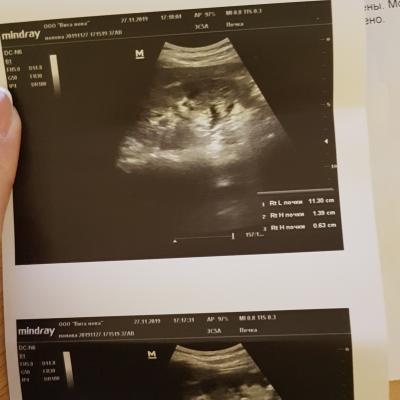

Добрый вечер! Недавно у меня заболела поясница слева. Обратилась к терапевту. Она назначила общий анализ мочи и пропить милдокалм, мелоксикам. Анализ пришел в норме. Мне сказали, что это остеохондроз. Я решила сделать узи почек и мочевого пузыря. Вот заключение: гидронефротическая трансформация левой почки, уз-признаки хр. пиелонефрита левой почки. Скажите, пожалуйста, что то надо с этим делать? Спасибо!

Здравствуйте! Надо сделать МСКТ(мультиспиральную компьютерную томографию ) почек и мочеточников для уточнения уродинамики верхних мочевых путей. С результатом обратитесь к урологу очно. Удачи!